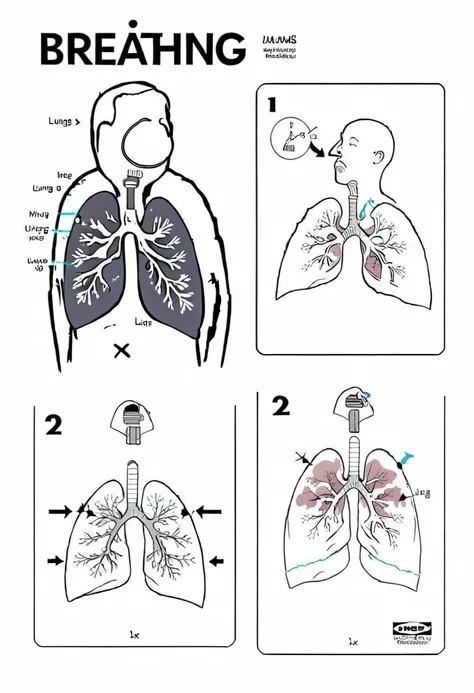

Make a folder about bacterial pneumonia

Make a folder about bacterial pneumonia

Make a folder about bacterial pneumonia